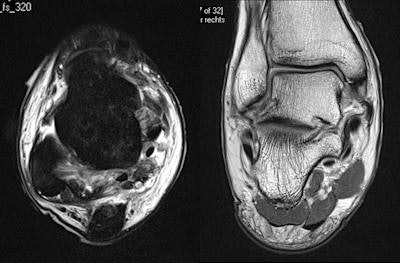

Un jugador profesional de football de 24 años es golpeado en el costado. El jugador siente de inmediato dolor en el tobillo y es sacado en camilla del campo. Es evidente que hay ligamentos mediales y laterales inflamados y magullados y una herida compleja de inversión/eversión en el pie. Imágenes por RM demuestran una herida del ligamento lateral y medial grado II. También se observan un desgarro total del ligamento talofibular anterior y un desgarro parcial del ligamento calcaneofibular. Las imágenes por RM son la prueba óptima de la integridad de los ligamentos mediales y laterales; pero si existe una herida ósea, la TC puede ser necesariaOtra unidad de ultrasonido estará localizada en Weymouth, Dorset, en donde tendrán lugar los eventos de vela. Un sistema de radiografía digital estará disponible en el Hospital de Weymouth, pero los sistemas de RM y TC más cercanos estarán en Dorchester. También habrá un escáner de ultrasonido en Eton Dorney, lugar en donde se llevarán a cabo los eventos de remo y canotaje. Para aquellos casos que no involucran el sistema musculo esquelético, se realizarán algunas evaluaciones iniciales, incluidas los rayos-x de tórax, en la sección de accidentes y urgencias del policlínico, pero los atletas se transferirán para el tratamiento a los hospitales universitarios Royal London o Homerton, que se encuentran en la cercanía.